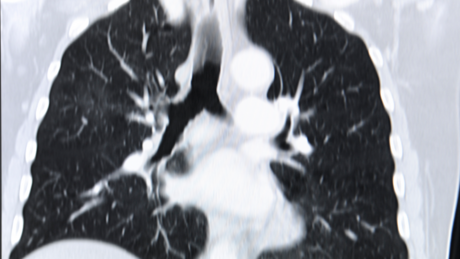

Kardio-CT

Der Klinik für Innere Medizin, Herz- und Kreislauferkrankungen steht ein für die Herz- und Gefäßbildgebung geeigneter Computertomograf der Firma Siemens zur Verfügung. Es handelt sich um ein sogenanntes 64-Zeilen-CT.

Das Gerät wird unter dem Dach der Klinik für Diagnostische Radiologie betrieben, die Herz-Untersuchungen werden gemeinsam von Kardiologen und Radiologen durchgeführt.

In weniger als 500 ms, also ungefähr der Zeit eines halben Herzschlages, dreht sich das Gerät einmal komplett um den ganzen Körper. Dabei dient der Röntgenstrahl unter Einsatz eines besonderen Detektorsystems der simultanen Erfassung mehrerer Schichten pro Umdrehung ("Mehrschicht-CT", "MSCT" oder "Multidetektor-CT", "MDCT"). Moderne Mehrzeilendetektoren ermöglichen sehr dünne Schichten (< 1 mm), mit denen innerhalb weniger Sekunden ein ausreichend großer Bereich des Körpers abgebildet werden kann. Mit diesem Verfahren können die Koronararterien in hervorragender Qualität abgebildet werden.

Aufgrund der kurzen Untersuchungszeit reduziert sich die notwendige Strahlenexposition oft um ein Vielfaches. Es ist besonders wichtig, dass eine CT-Koronarangiographie in ein sinnvolles diagnostisches und therapeutisches Gesamtkonzept eingebunden wird.

Das Herz-CT ist nur so gut, wie die Frage, die an diese Methode gestellt wird. Wir wenden den für den Patienten entscheidenden Fragen („Was bedeutet der Befund für mich?“ und „Welche Konsequenz hat dieser Befund?“) deshalb besondere Aufmerksamkeit zu. Nach der Untersuchung werden deshalb von einem Kardiologen mit Ihnen gemeinsam der Befund und seine Konsequenzen ausführlich erläutert.